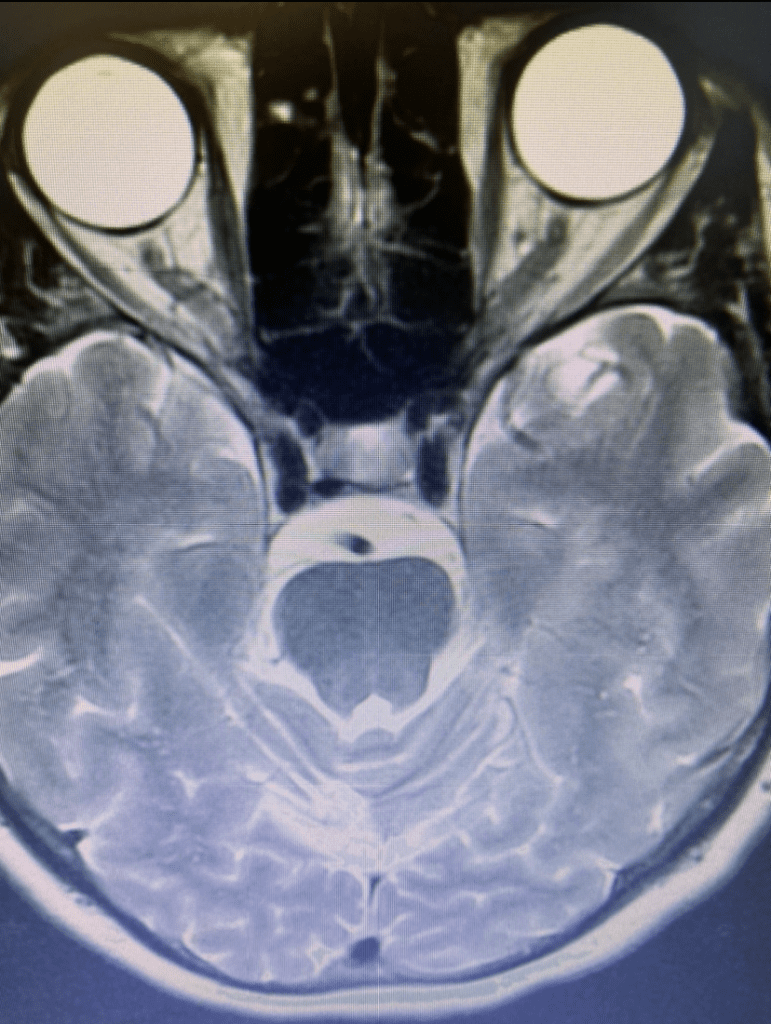

She returned for a follow up visit 19 years after the Gamma Knife treatment just to check up on things. She felt well and was neurologically intact. MRI and CTA of the brain were performed, which demonstrated complete obliteration of the AVM.

Figure 2B. Axial T2 MRI.